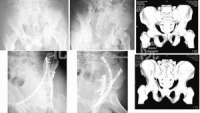

(1)骨盆后前位X线片:X线平片检查一般可明确骨折部位骨折类型及其移位情况,亦常能提示可能发生鵻的并发症。全骨盆后前位X线片可显示骨盆全貌对疑有骨盆骨折者应常规拍摄全骨盆后前位X线片以防漏诊对骨盆后前位X线片上显示有骨盆环骨折者,为明确了解骨折移位情况还应再摄骨盆入口位和出口位片。(2)骨盆入口位片:患者仰卧,X射线从颅侧投向尾侧,与片盒成60°倾斜摄片本位片可显示耻骨段骨折移位;骨盆向内、向外旋转和向内移位的程度;骶髂关节向后移位及骶骨骨折是否侵犯椎管;同样可显示坐骨棘撕脱骨折。

(3)骨盆出口位片:X线是从尾侧投向颅侧,与片盒成45°角本片可显示桶柄型损伤与耻骨体骨折,对确定半骨盆有无向上旋转移位是很有用的,在本片上同样可显示骶骨或髂骨骨折移位情况。

CT检查对骨盆骨折虽不属常规但它可在多个平面上清晰显示骶髂关节及其周围骨折或髋臼骨折的移位情况,因此凡涉及后环和髋臼的骨折应行CT检查骨盆三维重建CT或螺旋CT检查更能从整体显示骨盆损伤后的全貌,对指导骨折治疗颇有助益但应铭记对血流动力学鵻不稳定和多发伤患者,后前位全骨盆X线片是最基本和最重要鵻的放射学检查不要在拍摄特殊X线片上花费时间,更为重要的是尽快复苏。